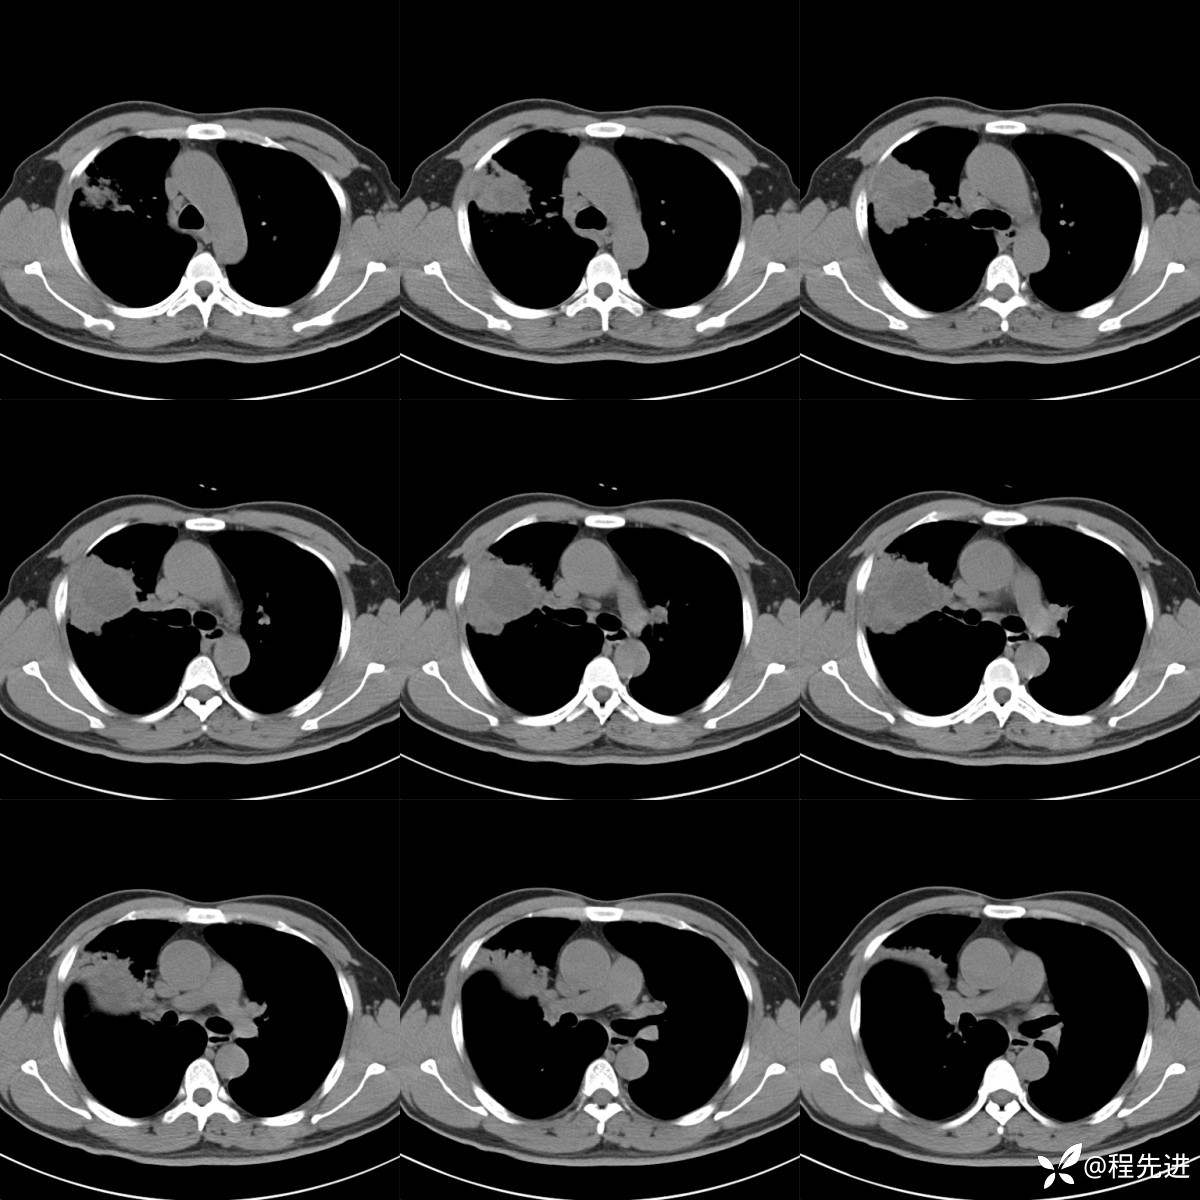

纵隔窗(厚层,图像连续):